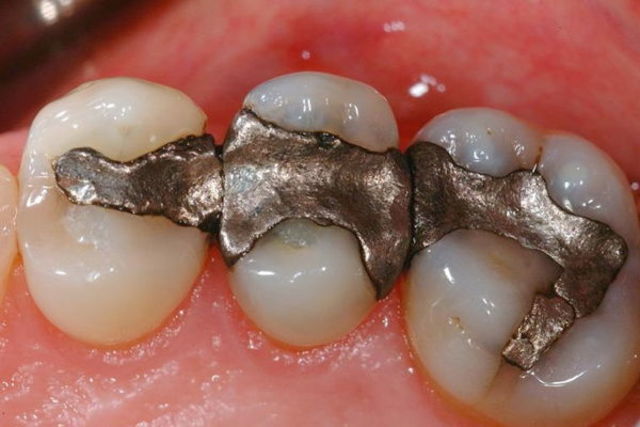

La amalgama de plata para obstrucciones es usada por primera vez por el Dr Thomas W. Evans.

Se realiza la mejora en el diseño de amalgamas usando compuesto de un 68% de plata por G.B. Black.